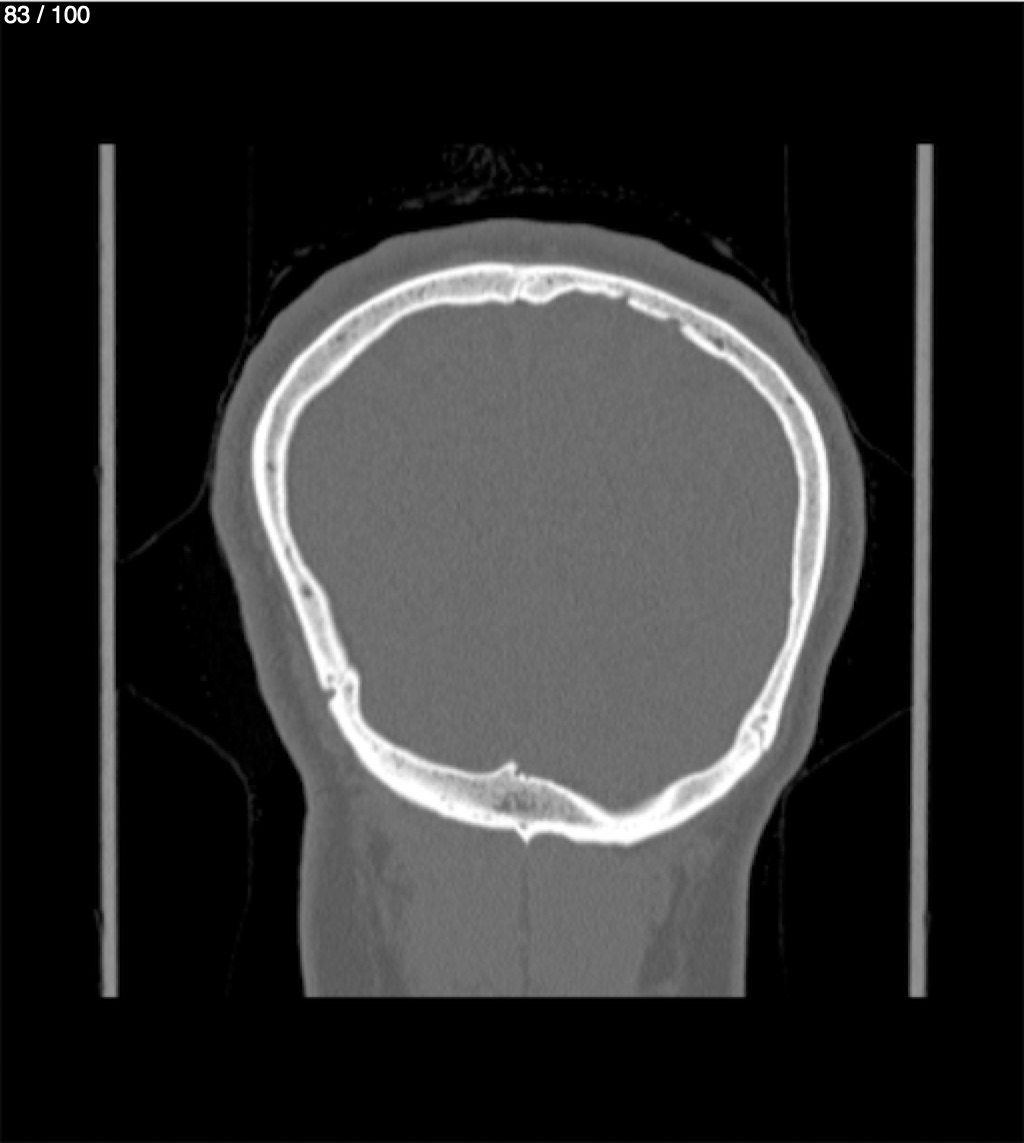

Yonelly Barrios Diaz 35A - T.C Craneo